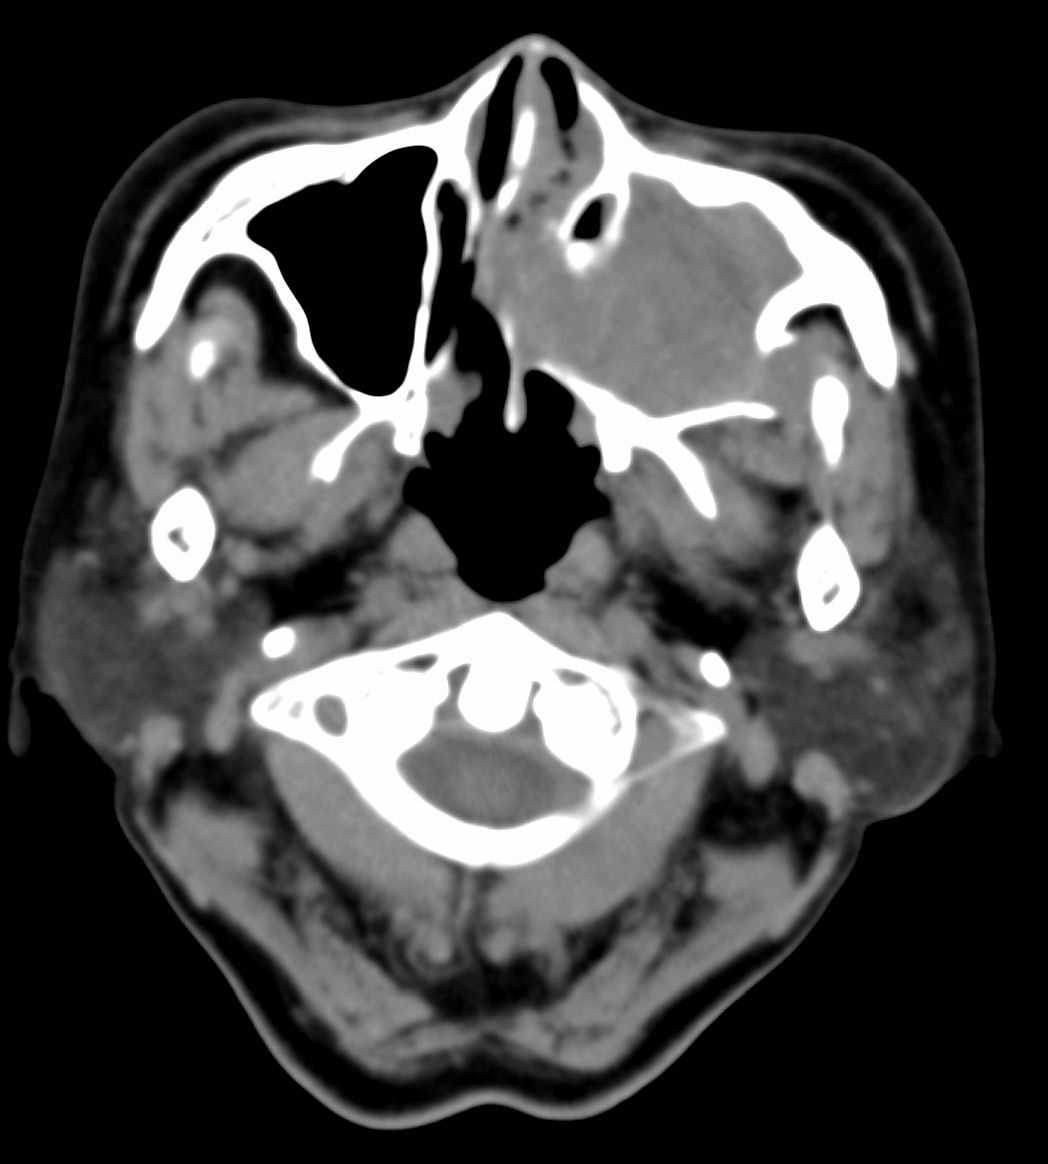

女,69岁。鼻出血2月多。(会诊病史就这样简单)鼻副窦ct检查如下:

左侧鼻腔及上颌窦见软组织块影,左侧上颌窦腔扩大,骨质吸收,右侧上颌窦见半圆形软组织密度影,鼻中隔向右侧弯曲,左侧鼻和鼻窦内翻型乳头状瘤可能性大,建议增强。

左侧上颌窦及鼻腔内见软组织密度影,其内密度不均匀,见斑片状高密度影,右侧上颌窦腔明显扩大,窦壁吸收变薄,鼻中隔右偏,右侧上颌窦见一半圆形软组织密度影,边界清楚,其内密度均匀。诊断,1、左侧鼻腔及上颌窦内翻乳头状瘤可能性大,上颌窦癌,息肉及霉菌性上颌窦炎待除外。2、右侧上颌窦粘膜下囊肿。

1)考虑左侧上颌窦内翻乳突状瘤突入左侧鼻腔。2)副鼻窦炎,右侧上颌窦黏膜下囊肿。

病理:霉菌性左侧上颌窦炎伴左侧上颌窦纤维组织增生。

窦腔密度不均匀增高,无明显钙化征象,后外侧及内侧窦壁膨胀明显,局部破坏消失,筛窦受累及,但双侧对比发现左侧窦壁骨质有硬化增白现象,这可能是支持左侧霉菌性上颌窦炎的主要依据点。